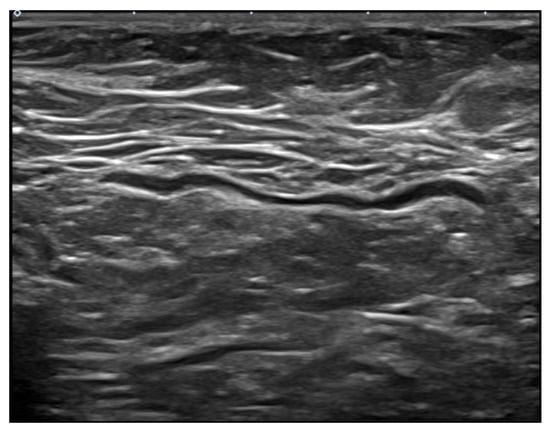

2.2. Ultrasound Technique